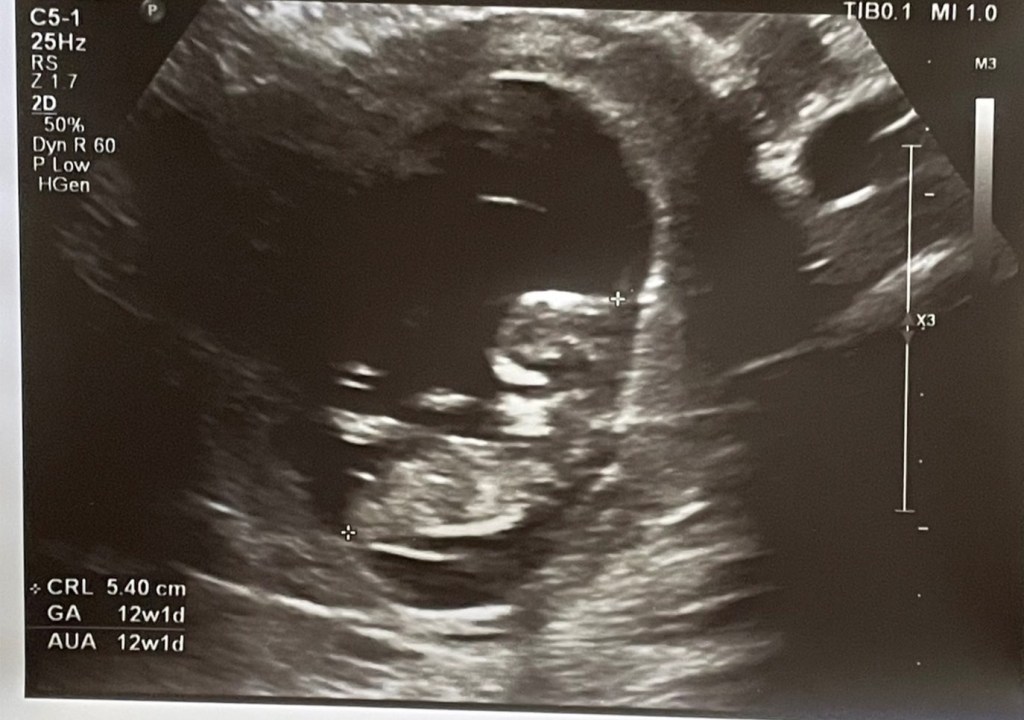

12週的超音波照已經可以看到寶寶的形狀了,醫生說羊水很充足,但我其實水喝很少,果然生命會自己找到出路,照超音波時還看到寶寶在抓頭,真有趣,看起來一切都很正常,就等下次16週產檢囉~ 可以看到寶寶的性別惹~